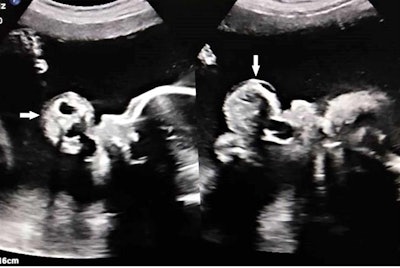

An ultrasound revealed a pedunculated 4.6 x 3.6-cm polypoidal mass protruding from the mouth of the fetus and freely floating in the amniotic cavity. The mass had a mixed solid-cystic echotexture, and it showed areas of calcifications and minimal vascularity. The woman also had an elevated level of amniotic fluid, with an amniotic fluid index greater than 28.5, according to the authors.